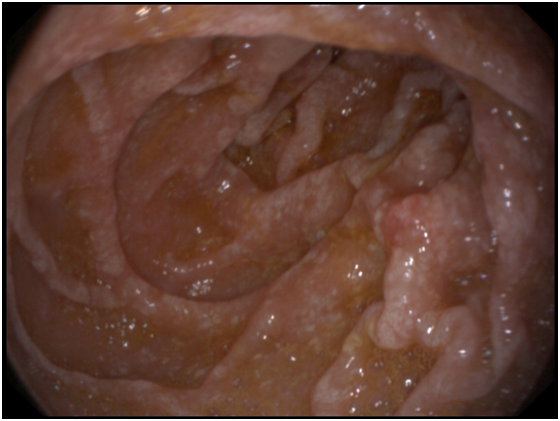

A 53- years old male presenting with chronic diarrhea of 8months duration, his diarrhea was of large volume, frothy in nature with foul odour. It was not related to a specific type of food, persisted during fasting with no diurnal variations. His condition was also associated with significant weight loss. The condition was associated with low grade fever and arthralgia of his both knee and hip joints. After 2months from the onset of his diarrhea he started to develop dizziness and easy fatigability. Physical examination of the patient was unremarkable apart from the pallor. Work up for diagnosing the cause of his diarrhea was done in the form of repeated stool analysis and culture, complete blood count, liver profile, renal profile, electrolytes, ESR, B2 microglobulins, virology (HIV, HBsAg, antiHCVab) and thyroid profile. All the previously mentioned investigations were normal apart from microcytic hypochromic anemia due to iron deficiency with haemoglobin=7.3mg/dl, serum Fe was 10mg/dl and transferrin saturation was 5%, also he had mild hypoproteinemia with serum total protein of 6.2g/dl and mild hypoalbuminemia with serum albumin of 3g/dl. His ESR was 123 and C-reactive protein (CRP) was 49mg/dl as shown in Table 1. Abdominal ultrasound was completely normal. Attempts of giving empirical medications in the form of metronidazole and quinolones failed to control the condition of the patient. Endoscopic intervention was decided in the form of upper endoscopy and colonoscopy. Total colonoscopy and terminal ileoscopy were done with no abnormality detected. For the upper endoscopy; the duodenal mucosa down to the proximal jejunum was markedly congested with extensive whitish mucosal patches as shown in Figure 1-3. Multiple biopsies were taken; histopathological examination showed focal villous distortion and focal villous erosions. The lamina propria showed mild mono-nuclear cell infiltrate with extensive infiltrate of foamy macrophages with dilated lymphatic spaces as shown in Figure 4. PAS (periodic acid shiff) stain was applied during microscopic examination where the organism was detected as shown in Figure 5. And hence the patient was diagnosed as a case of Whipple’s disease (WD). Then treatment was started accordingly in the form of ceftriaxone for 15days followed by trimethoprim-sulfamethoxazole (TMP/SMX) twice a day for 1 to 2years with marked improvement of the patient's condition. The improvement was evident by his laboratory parameters (Table 1) and endoscopic picture (Figure 6).

Figure 6 Complete disappearance of the shaggy mucosa of the duodenum after 3 months of treatment.